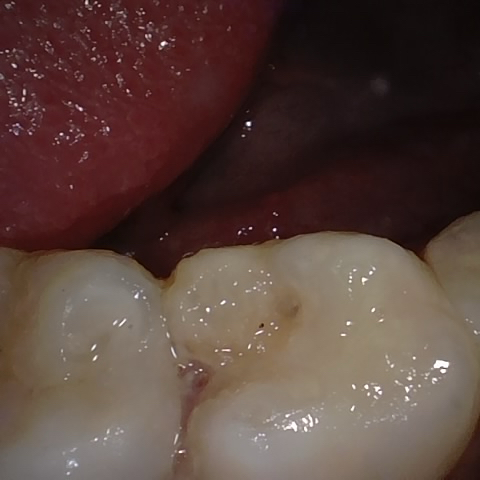

Annotated as "Good"